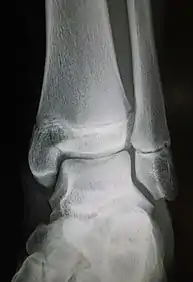

Fracture of the medial malleolus seen on X-ray scan (left ankle)

Common symptoms of a Maisonneuve fracture are pain, swelling, tenderness, and bruising around the ankle joint and inferior (or distal) tibiofibular joint. More specifically, as a pronation-external rotation injury, pain during external rotation of the ankle joint is expected. Additionally, there is a reduced range of motion of the foot and an inability to weight-bear due to ankle pain.[4][7] Pain may also be felt around the medial and lateral aspects of the ankle, and more rarely around the superior (or proximal) tibiofibular joint.[9] Damage to the deltoid ligament or interosseous membrane can cause haemorrhaging around the surrounding tissues, resulting in a localised oedema.[8]